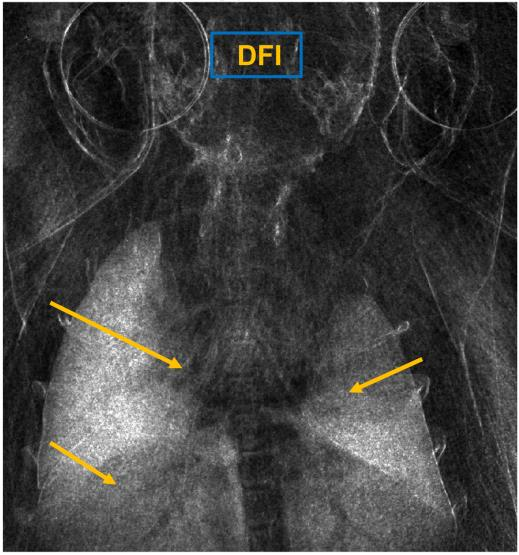

Low-dose computed tomography (LDCT) is the current standard for lung cancer screening, yet its adoption and accessibility remain limited. Many regions lack LDCT infrastructure, and even among those screened, early-stage cancer detection often yield false positives, as shown in the National Lung Screening Trial (NLST) with a sensitivity of 93.8 percent and a false-positive rate of 26.6 percent. We aim to investigate whether X-ray dark-field imaging (DFI) radiograph, a technique sensitive to small-angle scatter from alveolar microstructure and less susceptible to organ shadowing, can significantly improve early-stage lung tumor detection when coupled with deep-learning segmentation. Using paired attenuation (ATTN) and DFI radiograph images of euthanized mouse lungs, we generated realistic synthetic tumors with irregular boundaries and intensity profiles consistent with physical lung contrast. A U-Net segmentation network was trained on small patches using either ATTN, DFI, or a combination of ATTN and DFI channels.Results show that the DFI-only model achieved a true-positive detection rate of 83.7 percent, compared with 51 percent for ATTN-only, while maintaining comparable specificity (90.5 versus 92.9 percent). The combined ATTN and DFI input achieved 79.6 percent sensitivity and 97.6 percent specificity. In conclusion, DFI substantially improves early-tumor detectability in comparison to standard attenuation radiography and shows potential as an accessible, low-cost, low-dose alternative for pre-clinical or limited-resource screening where LDCT is unavailable.